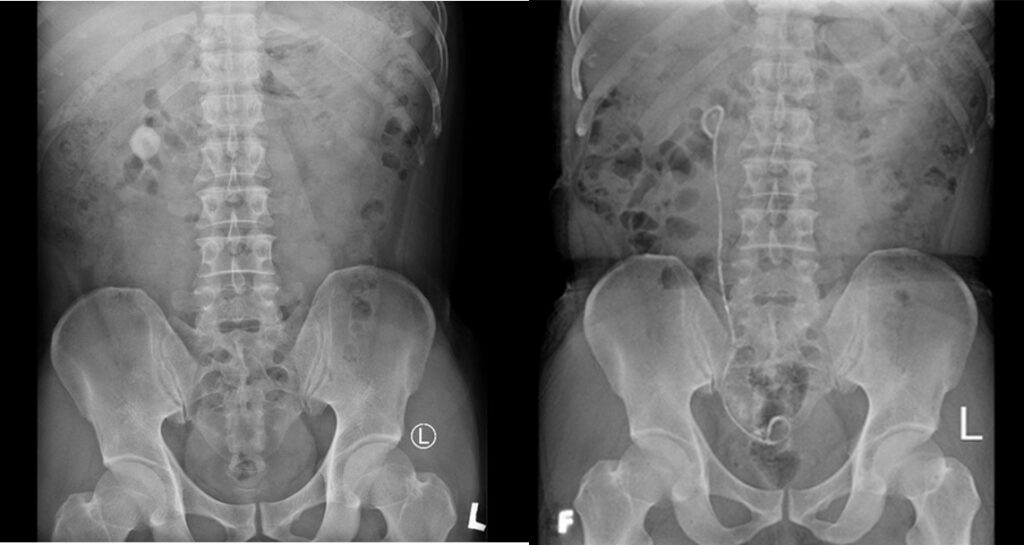

BSCKII Lê Đình VŨ Trưởng khoa Ngoại Tiết niệu Giới thiệu Sỏi thận